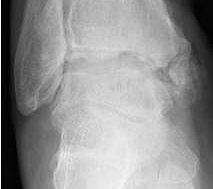

• Primäre oder posttraumatische Arthrose des OSG und USG (Abbildung 1, Abbildung 2).